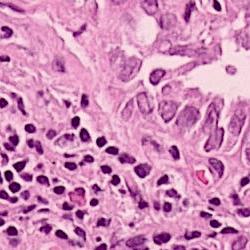

Histopathology plays a vital role in cancer diagnosis, prognosis, and treatment decisions. Histopathology slides are created from formalin-fixed paraffin-embedded (FFPE) tissue containing both tumor and surrounding normal tissue. These slides are then stained with agents such as hematoxylin and eosin (H&E) and immunohistochemical stains that permit the pathologist to ascertain important features. For instance, pathologists routinely determine the type of cancer, stage of cancer, cancer’s grade, presence of infiltrating immune cells, and potential treatment options based on histopathology slides. Whole slide imaging allows the pathologist to view the slides digitally as opposed to what was traditionally viewed under a microscope. With improvements in computational power and image analysis algorithms, computational methods [1, 2, 3, 4] have been developed for the quantitative and objective analyses of histopathology images, which can reduce the intensive labor and improve the efficiency for pathologists compared with manual examinations. Nuclei segmentation is a critical step in the automatic analysis of histopathology images, because the nuclear features such as average size, density and nucleus-to-cytoplasm ratio are related to the clinical diagnosis and management of cancer. Besides, clinical sequencing of cancer specimens is becoming routine and nuclei segmentation algorithms will play a key role in the proper interpretation of these sequencing results.

To validate the proposed framework, we conduct experiments on two datasets of H&E stained histopathology images.

We generated this dataset by extracting 40 images of size from 8 lung adenocarcinoma or lung squamous cell carcinoma cases, i.e., H&E stained WSIs with 20x magnification. They are split into the training, validation and test sets, consisting of 24, 8 and 8 images, respectively. 24401 nuclei are annotated with masks.

It is a public dataset released by Kumar et al. [10], and consists of 30 images of size which are taken from multiple hospitals including a diversity of nuclear appearances from seven organs [10]. The variability in this dataset is large because of the heterogeneity between organs and cancer types. There are 12, 4 and 14 images in training, validation and test sets.